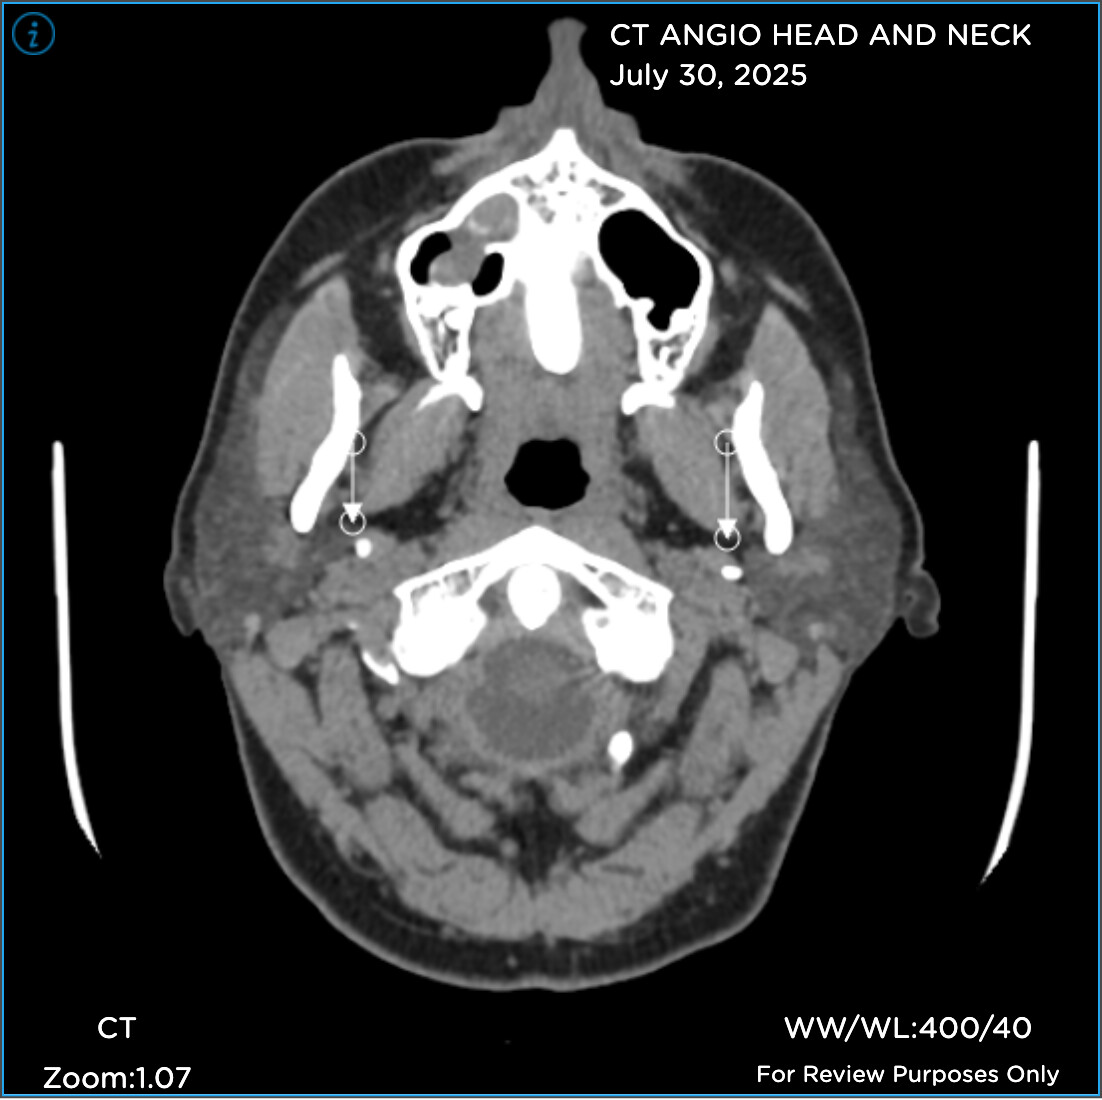

Hi folks. Like many of you, I’ve been on a miserable journey for years now. I’m just diagnosed “officially” with Eagles yet, but my provider said she sees elongated styloids on both sides, and she has referred me to Hepworth and recommends styloidecomy(ies).

Prior to seeing her, I’d been dealing with a CSF leak (5 blood patches to date), chronic migraines, Central Sensitization Syndrome/fibro (basically whole body pain), etc. When my FMC looked at the imaging I finally uploaded, she immediately noticed elongated styloids on both sides and she recommends styloidectomy(ies).